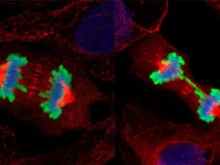

Hospital do Papa anuncia importante descoberta na luta contra o câncer

Uma nova pesquisa do Hospital Pediátrico Bambino Gesù permitirá desenvolver novos tratamentos contra o câncer. Trata-se da descoberta sobre o mecanismo de... Leia mais

Estudo mostra que antes de nascer já há diferenças entre o cérebro masculino e feminino

Um novo estudo científico encontrou diferenças significativas na maneira como os cérebros masculinos e femininos funcionam no útero durante a... Leia mais